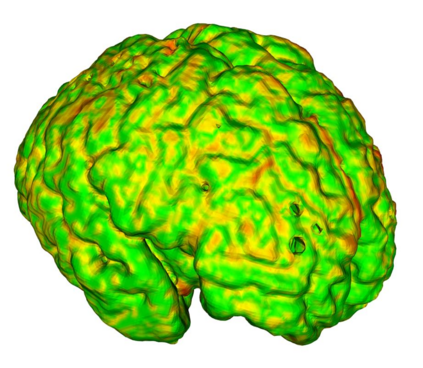

Fetal cortical plate segmentation is essential in quantitative analysis of fetal brain maturation and cortical folding. Manual segmentation of the cortical plate, or manual refinement of automatic segmentations is tedious and time-consuming. Automatic segmentation of the cortical plate, on the other hand, is challenged by the relatively low resolution of the reconstructed fetal brain MRI scans compared to the thin structure of the cortical plate, partial voluming, and the wide range of variations in the morphology of the cortical plate as the brain matures during gestation. To reduce the burden of manual refinement of segmentations, we have developed a new and powerful deep learning segmentation method. Our method exploits new deep attentive modules with mixed kernel convolutions within a fully convolutional neural network architecture that utilizes deep supervision and residual connections. We evaluated our method quantitatively based on several performance measures and expert evaluations. Results show that our method outperforms several state-of-the-art deep models for segmentation, as well as a state-of-the-art multi-atlas segmentation technique. We achieved average Dice similarity coefficient of 0.87, average Hausdorff distance of 0.96 mm, and average symmetric surface difference of 0.28 mm on reconstructed fetal brain MRI scans of fetuses scanned in the gestational age range of 16 to 39 weeks. With a computation time of less than 1 minute per fetal brain, our method can facilitate and accelerate large-scale studies on normal and altered fetal brain cortical maturation and folding.